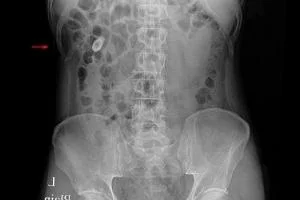

کوچک شدن کلیه چگونه تشخیص داده می شود؟

آزمایش های مخصوص آتروفی کلیه شامل آزمایش های عکسبرداری مثل سونوگرافی، توموگرافی یا همان سی تی اسکن یا ام آر آی است.